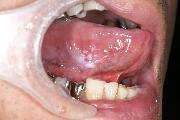

8.舌を上に挙げて裏側を見ます。見落としやすい場所です。

舌がん(舌のがん)